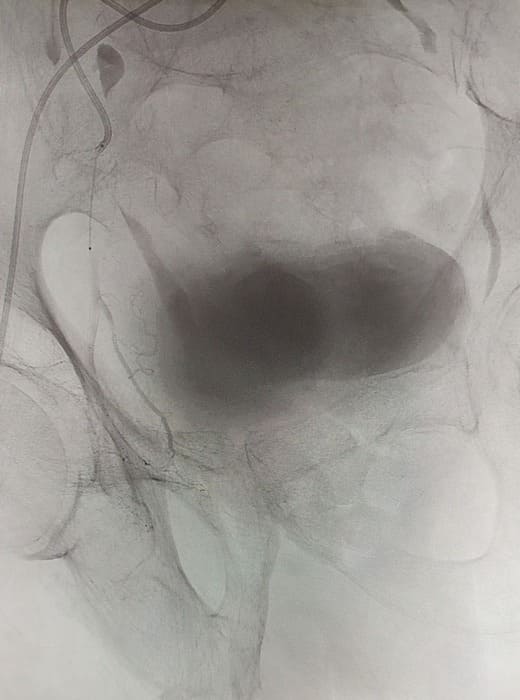

Зазвичай люди літнього віку мають вражені атеросклерозом та звивисті, внаслідок гіпертонічної хвороби судини. Цей випадок не був виключенням, тому нам довелося докласти максимум зусиль, використати високотехнологічне обладнання та інструменти, щоб віднайти цільові судини. На диво, незважаючи на попередню операцію, судинний малюнок рецидивної простати збігався з тим який буває у не оперованих пацієнтів. Тому нам вдалося їх чітко визначити з обох сторін та заповнити емболами. Це доволі кропітка праця, адже щоб викликати ішемію, необхідно поступово виключити кровоплин в усій тканині залози. Полегшувало операцію лише відсутність перетоків артерій на сусідні органи. Це дозволило нам безпечно емболізувати, не боячись негативних наслідків та ускладненнь.

Операція була виконана 28.05.2021. під місцевою анестезією, доступом через прокол в правій стегновій артерії. Вже на протязі тижня зменшилась кількість походів в туалет по маленькому (вночі до 1 разу), полегшилось сечовиділення та покращилось самопочуття хворого.